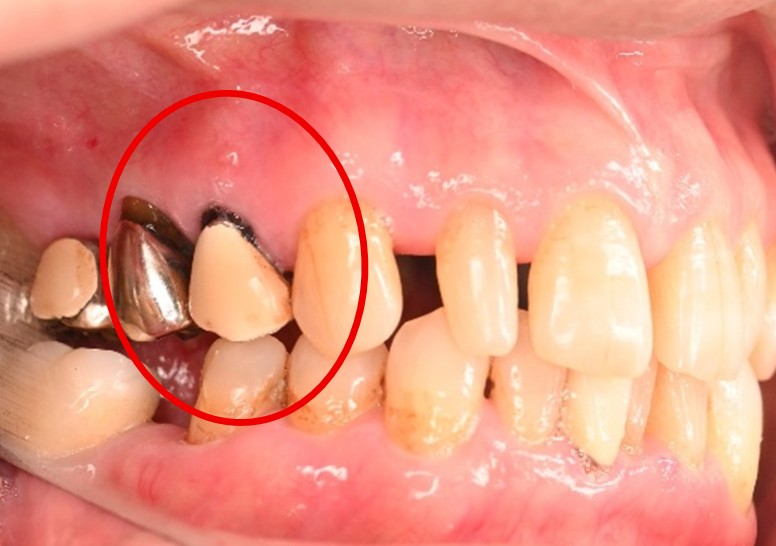

女性 Yさん 60代 (オールセラミック冠)

主訴

以前治療した右下の犬歯が、虫歯になり色が変わってきているので、治したい。

治療内容

根管治療をし、オールセラミック冠を被せました。

所感

神経が取り除かれ、歯自体が変色し、虫歯になっていました。根管治療をし、ファイバーコアを入れ、オールセラミック冠を被せました。

オールセラミック冠1本(失活歯):¥104,500(税込)

Before

After